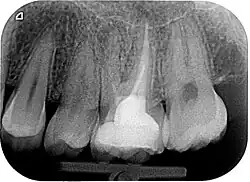

Zur Beurteilung des Erfolges einer Wurzelkanalbehandlung werden klinische Beschwerden, wie Schmerzen, Schwellungen oder Fistelgänge sowie der röntgenologische Befund herangezogen. Oft sind trotz endodontischer Infektion keine klinischen Beschwerden vorhanden, weshalb gerade die röntgenologische Kontrolle Hauptkriterium für die Beurteilung ist.[10] Neben der vorhandenen Wurzelfüllung und Veränderungen in der Wurzelphysiognomie (Resorptionen) wird vor allem der Zustand des periapikalen Gewebes begutachtet und auf das Vorhandensein einer Parodontitis apikalis oder einer radikulären Zyste geprüft.

- Wurzelkanalbehandelte Zähne mit röntgenologisch oder klinisch insuffizienter Wurzelkanalfüllung (z. B. mangelhafte Homogenität der Füllung, nicht behandelte Wurzelkanäle, nicht gefüllte Areale des endodontischen Systems, fragwürdiges und nicht mehr indiziertes Füllmaterial etc.) ohne klinische oder röntgenologische Anzeichen einer Parodontitis apicalis.

Wenn eine Verbesserung des Ausgangszustandes und eine Beseitigung der möglichen Ursachen nicht zu erwarten sind oder die Erhaltung des Zahns fragwürdig ist, ist von einer Revision abzusehen. Ebenso müssen nicht-endodontische Ursachen der Erkrankung vor einem Eingriff ausgeschlossen werden.[1] Nach Strindberg et al. wird der endodontische Misserfolg nach einer ausreichenden Heilungszeit von vier Jahren mit dem Vorhandensein einer residuellen, persistierenden oder progredienten röntgenologischen Aufhellung (Dunkler Punkt an der Wurzelspitze im Röntgenbild) und/oder mit dem Vorhandensein klinischer Beschwerden jeglicher Form definiert.[18]